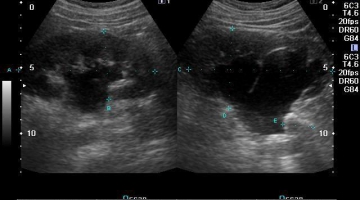

Ο Ιατρός Γουλόπουλος Χρήστος διατηρεί Ακτινοδιαγνωστικό Ιατρείο-Κέντρο Υπερήχων και Τρίπλεξ παντός τύπου,στην καρδία του Αμπελώνα με εύκολη πρόσβαση σε πεζούς και ελεύθερο χώρο στάθμευσης.

Στόχος μας είναι η πρόληψη, ευαισθητοποίηση και σαφώς η διαφύλαξη της υγείας του εξεταζομένου, με αποτέλεσμα την έγκυρη και σωστή διάγνωση.

.Ειδικός Ιατρός Ακτινοδιαγώστης στη Euromedica Καρδίτσας, με ιδιαιτερότητα στους υπερήχους μαστών και θυρεοειδούς αδένα